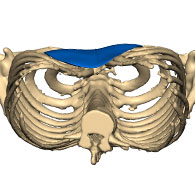

Tutti possono essere colpiti da questa patologia. La letteratura scientifica stima un rapporto di 4 uomini per ogni donna (75%). Il Pectus è caratterizzato da una crescita insufficiente o eccessiva delle strutture ossee e/o cartilaginee della gabbia toracica. Colpisce la seconda parte dello sterno e invade le cartilagini dalla terza all’ottava costola. La scoliosi è spesso associata a questa deformazione.

CHIN 3: la malformazione è asimmetrica e si estende alle regioni pettorali. La deviazione è più spesso sul lato destro.

Esistono altri tipi talvolta associati: misti (combinazione più tipologie della classificazione di Chin come il lato destro profondo e il lato sinistro più esteso), arcuatum (con bassa depressione xifoide) o ibridi (associati alla sindrome di Poland con agenesia del muscolo grande pettorale).